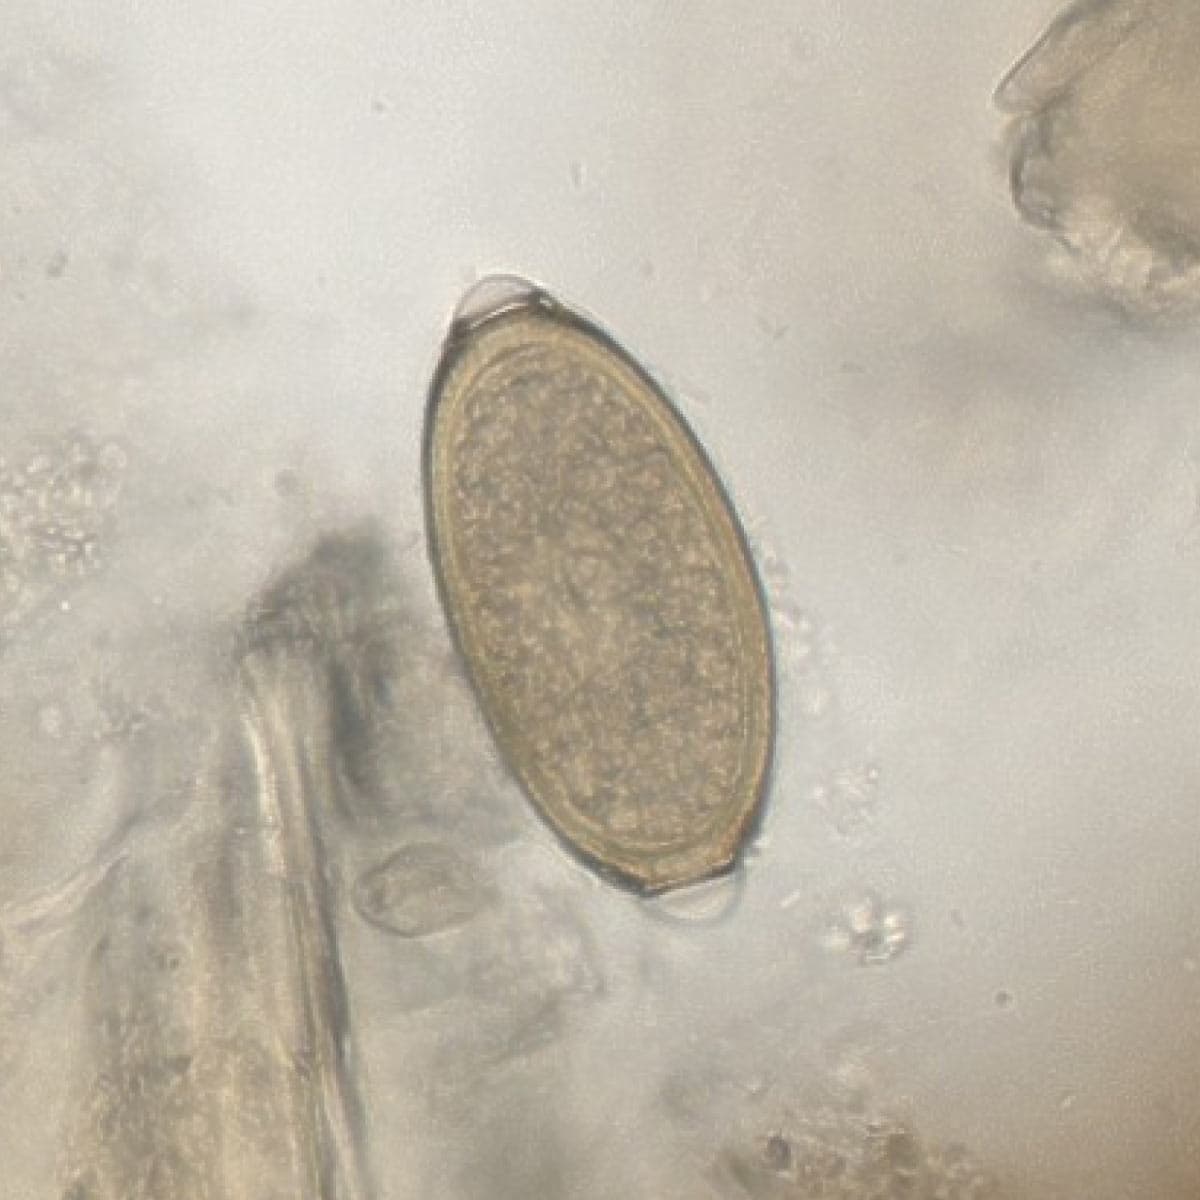

Automatic detection of rare species

Built on worldwide parasite-positive specimens, ParaScout AI identifies a vast number of parasite species, including those that are clinically rare or challenging to find.